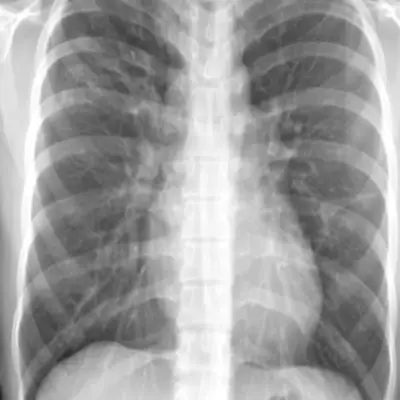

결핵 증상 및 원인 아셔야 예방과 치료가 가능합니다. 결핵은 결핵균에 의해 유발되는 감염성 질환으로, 사람의 폐를 주로 공격하는 질병입니다. 이 질병은 다양한 증상을 유발하여 환자의 건강을 심각하게 해칠 수 있습니다.

이 글에서는 결핵 증상 및 원인에 대해서 자세히 알아보겠습니다. 이 글로 인해 조금이나마 건강에 도움이 되었으면 하는 바람입니다.